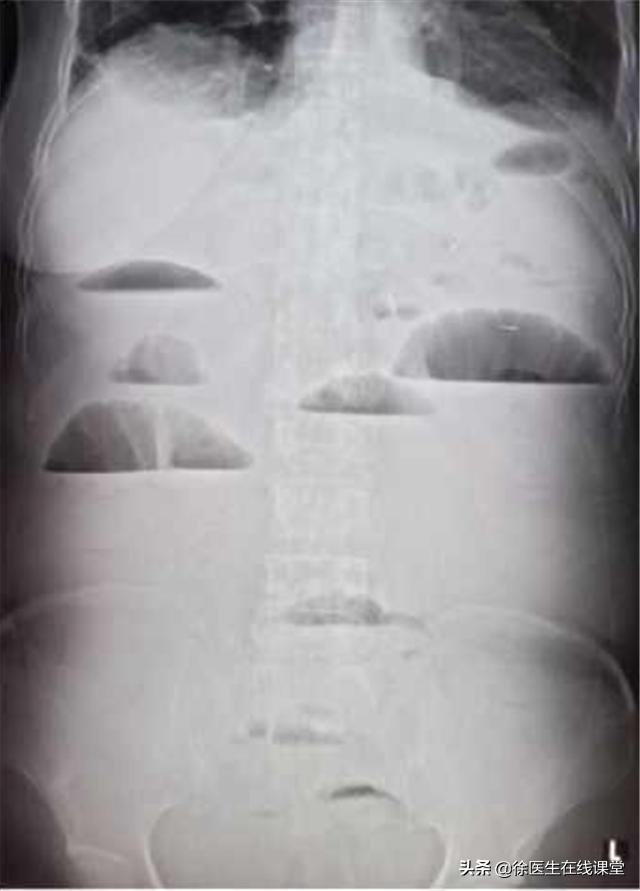

肠癌患者由于肠道病变导致 肠道自身的蠕动功能降低 ,长久以往便会 引起腹部胀痛。 除此之外肠癌患者常伴有 低位肠梗阻 的相关症状,同样的肠梗阻也会造成患者腹部的疼痛感。 疼痛一般出现在患者的中下腹部,每个患者的疼痛表现不一,疼痛轻度不一。